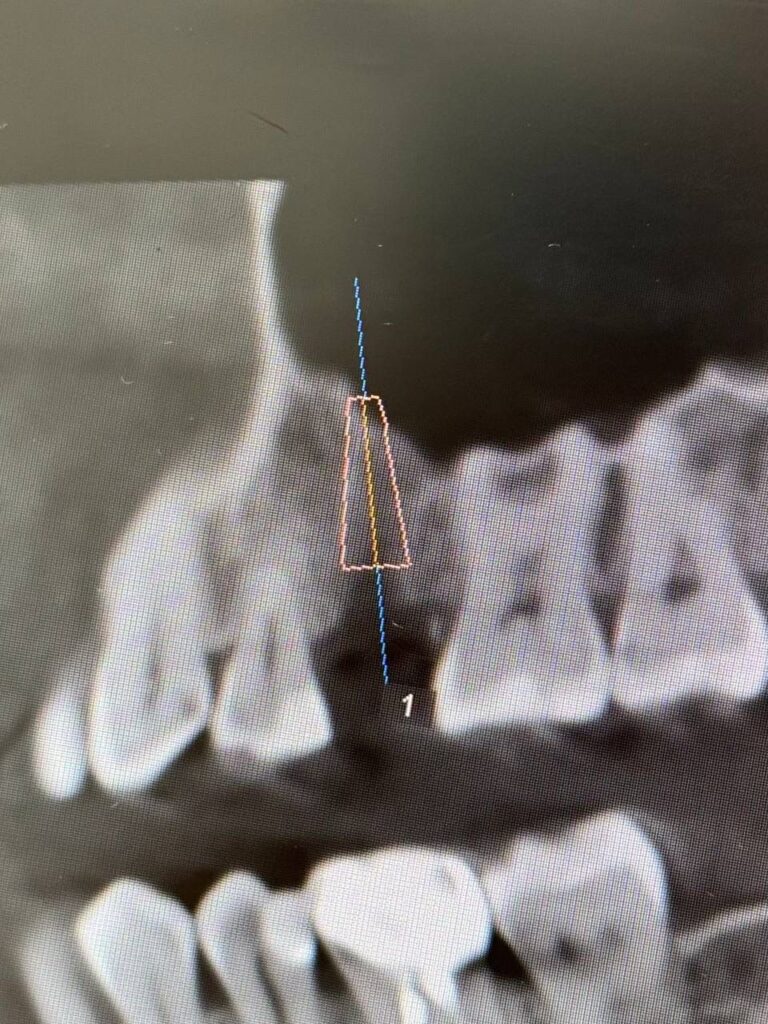

Специализация: терапия(эндодонтия), ортопедия, имплантология.